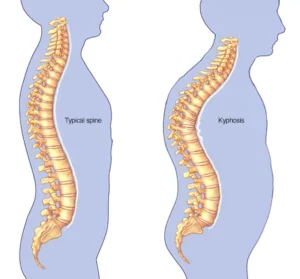

Kyphosis

kyphosis is often due to weakness in the spinal bones that causes them to compress or crack. Other types of kyphosis can appear in infants or teens. These types are due to malformation of the spine or wedging of the spinal bones over time.